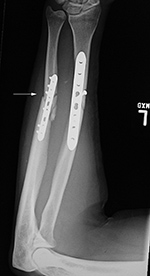

A short one-third tubular plate and screws plus interfragmentary screw stabilize a healing distal fibular fracture. An associated stress fracture (arrow) is in the distal tibial metaphysis from altered weight-bearing from the fibular fracture. |